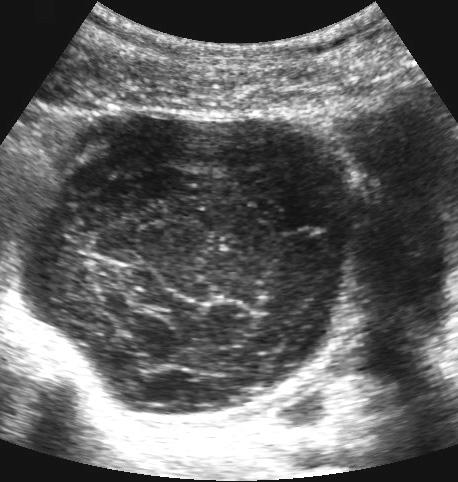

Ca lâm sàng 4

Nang xuất huyết chức năng này là phát hiện tình cờ và có thể dễ dàng ép xẹp vào mỏm nhô (p).

Các bất thường biến mất hoàn toàn trong vòng hai tuần.